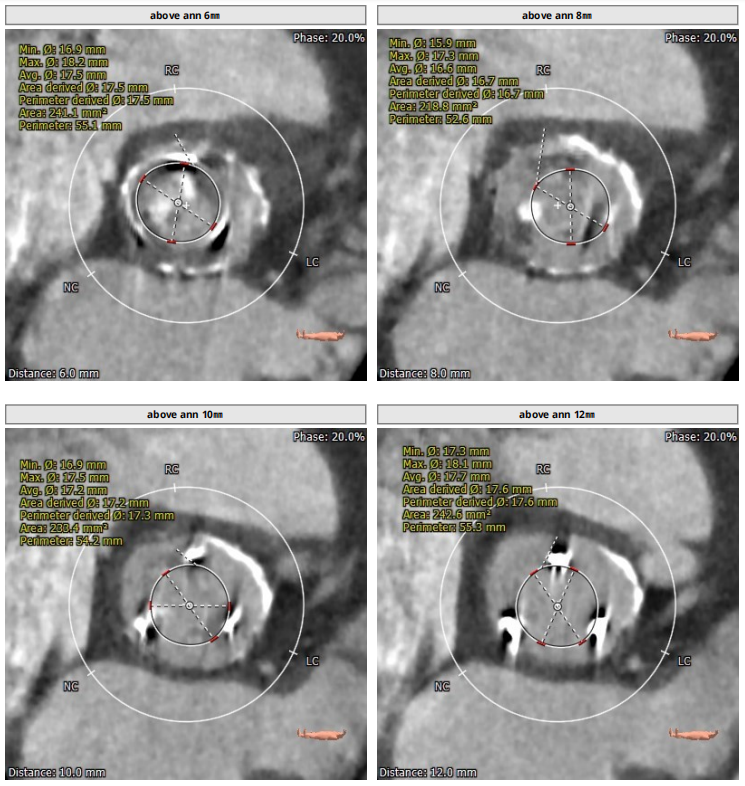

术前CT评估报告

1、入路条件差,髂动脉血管钙化十分严重,通路建立难度极大。

2、主动脉瓣置换术后,瓣口面积极小,导致瓣膜无法稳定锚定,需要术中时刻观察调整。

3、升主动脉最宽处约44.5mm,心脏角度大,约50°,备Snare辅助。